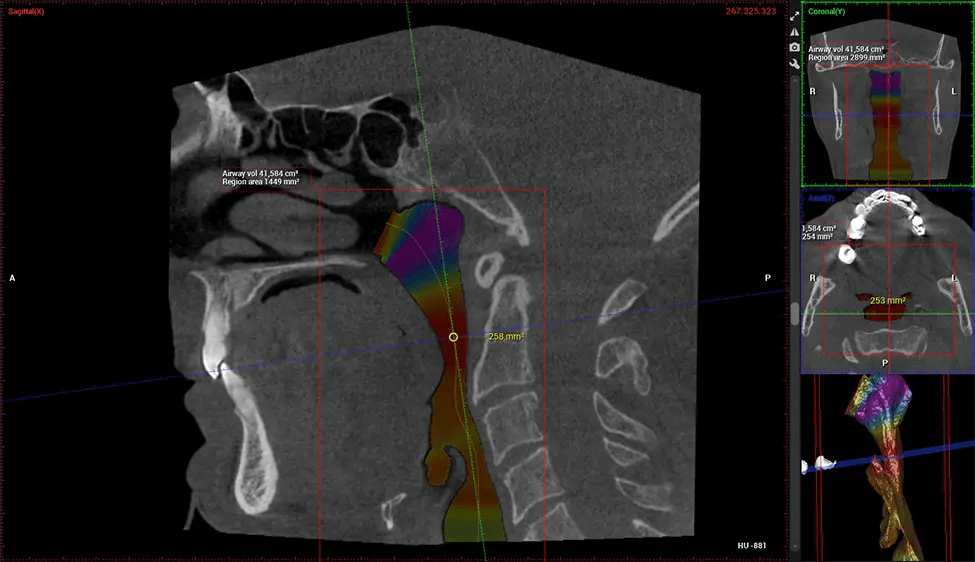

Cone Beam Computed Tomography (CBCT) is an advanced imaging technique used in dentistry and maxillofacial surgery to obtain detailed 3D images of the oral and maxillofacial structures. At Dr G Dental Studio, our CBCT scanners utilize a cone-shaped X-ray beam and a specialized detector to capture images from different angles. A computer then combines these images to create a 3D representation of the patient’s oral anatomy.

After the scanning process, the captured X-ray images are processed by the CBCT software, which applies algorithms to reconstruct a detailed 3D image of the scanned area. The software compiles these individual X-ray images and creates a digital 3D representation of the patient’s anatomy. The reconstructed 3D CBCT image can be viewed and analyzed by the dentist or radiologist. This image can be manipulated, rotated, and zoomed in or out to examine specific structures and evaluate the patient’s condition.

ENT Physician Diagnosing obstructive sleep apnea (OSA) and evaluating sinus and nasal cavity anatomy. Visualizes the entire pharyngeal airway to measure volume, pinpoint constrictions, and plan corrective surgery if needed.

Screening and treating patients at risk for OSA.

Provides detailed 3D imaging for airway analysis, helping to create and adjust oral appliances and facilitate effective referrals to medical doctors.